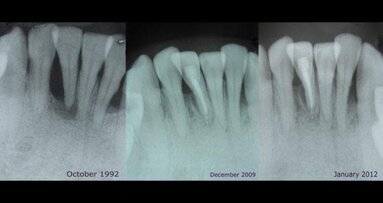

Suite à ce qui semblait être un échec du traitement radiculaire de la dent 26, basé sur un diagnostic clinique et radiologique avec une radiographie périapicale classique en 2D (Fig. 1), le patient était considéré comme à référer à un endodontiste

L'étude CBCT comprenait des coupes transversales de la dent N° 26, à 0.5 mm d'intervalle, révélant une communication endo-paro et démontré que la maladie périapicale, étendus vers le sinus et dans la région de la furcation, a causé la résorption osseuse qui s'étend jusqu'au bord gingival palatin (figures 2,3).